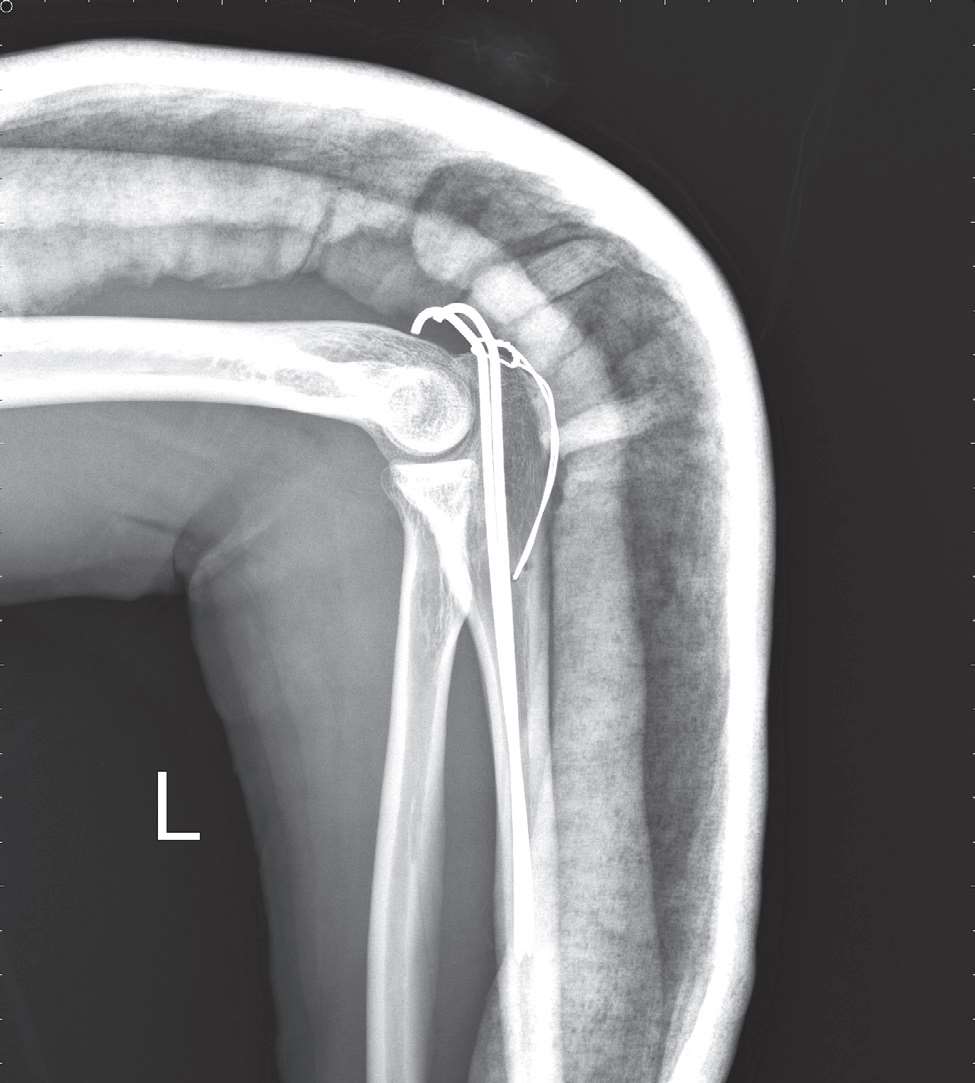

2.手术治疗 尺骨鹰嘴骨折切开复位内固定术(图8-2)。

图8-2 尺骨鹰嘴骨折术后X线片